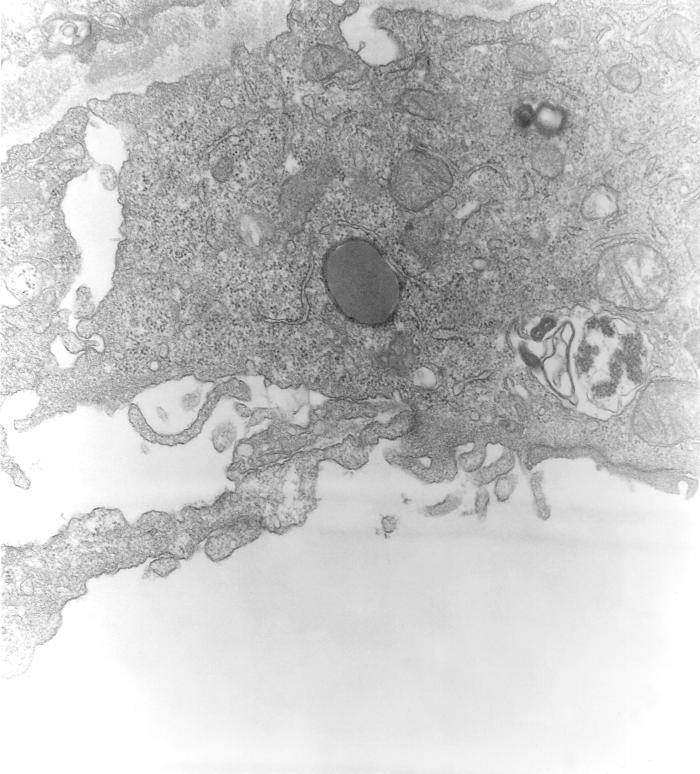

This 1976 transmission electron microscopic (TEM) image depicted a hypertrophic peritoneal mesothelial cell from a mouse that had been experimentally infected with Orientia tsutsugamushi rickettsial micro-organisms. A disintegrating organism can be seen within one of its host cell's phagocytic vacuole. Formerly known as Rickettsia tsutsugamushi, O. tsutsugamushi is the pathogen responsible for causing the febrile disease known as scrub typhus. The disease is transmitted to humans through the bite of larval trombiculid mites, i.e., chiggers, that had fed on infected rodents.